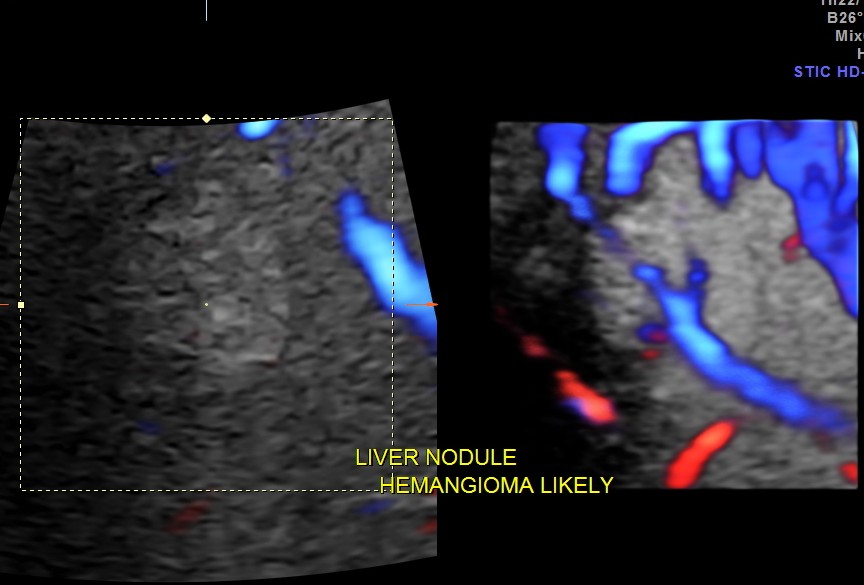

Hemangioma of the liver is generally an innocuous incidental finding . At times the differential diagnosis considered would include a solitary secondary nodule. This would require further imaging investigations like CT and MRI. Colour and Power Doppler could be helpful in demonstrating the feeding vessel to a hemangioma , but is very difficult to demonstrate at times. 3D 4 D glass body reconstruction could help in demonstrating the feeding vessel.

The pictures and the video are presented to show the clarity with which glass body reconstruction demonstrates the feeding vessel .